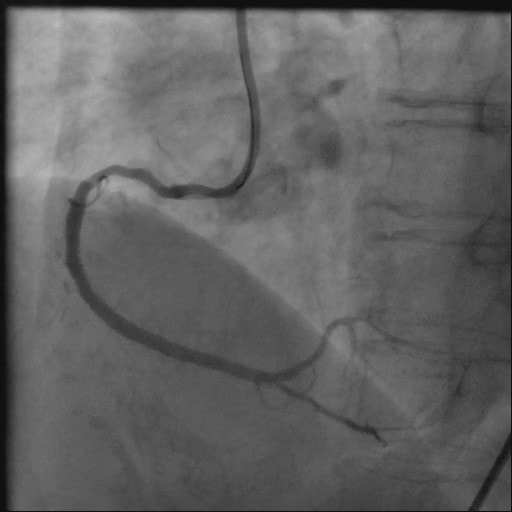

PCI前の冠動脈評価CT

PCI後の冠動脈評価CT

PCI施行前と後